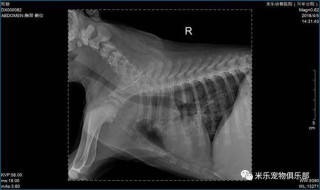

狗狗得了支气管炎怎么办,(狗狗得了支气管炎是什么症状)

大家好,今天给各位分享狗狗得了支气管炎怎么办的一些知识,其中也会对狗狗得了支气管炎是什么症状进行解释,文章篇幅可能偏长,如果能碰巧解决你现在面临的问题,别忘了关注本站,现在就马上开始吧!狗狗支气管肺炎多久能治愈狗...